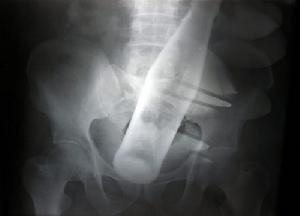

腹部X光腹部X光就是利用X光對腹部進行檢查的一種醫學診斷方法。X線診斷學(DiagnosticRoentgenology)是套用X線特性,通過人體後在透視螢光屏或照片上顯示正常和異常的影像,結合基礎醫學和臨床醫學的知識,加以分析、歸納,作出診斷的一種科學。它不僅用以診斷疾病,還可以觀察臨床的治療效果,亦可以用於預防醫學,如體檢、防癆、腫瘤、職業病和地方病等的普查防治。